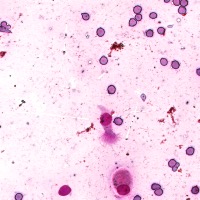

Medical Diagnosis: The "4class" model can be employed by pathologists to accurately identify and quantify the different cell types in blood and tissue samples, assisting in the diagnosis of various blood disorders and diseases, including anemia, leukemia, and infections.

Research and Drug Development: Researchers can use the "4class" model to analyze cellular response to experimental treatments, providing essential data for drug discovery, evaluating the efficacy of novel compounds, and understanding cell behavior under various conditions.

Education and Training: The "4class" computer vision model can serve as an educational tool for medical students and professionals, facilitating their understanding of different cell types, their characteristics, and functions, while promoting accurate identification in laboratory settings.

Automated Screening: Integration of the "4class" computer vision model into medical laboratory equipment can automate the process of cell classification during screenings or biopsies. This can help save time and reduce the risk of human errors during the evaluation of samples.

Telemedicine and Remote Analysis: The "4class" model can support telemedicine platforms, making it possible for healthcare professionals to remotely access and evaluate blood and tissue samples. This would be particularly useful in underserved areas, where access to pathologists might be limited.